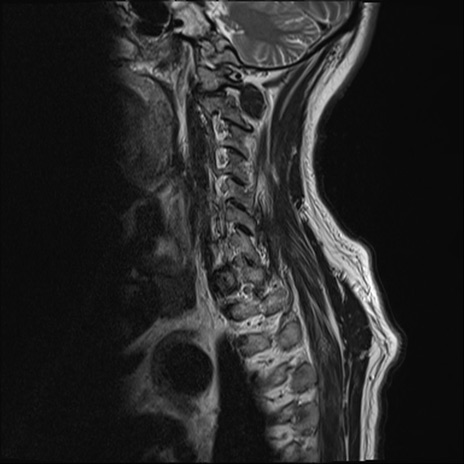

頚椎MRI

T2WI(横断像)

矢状断像と横断像